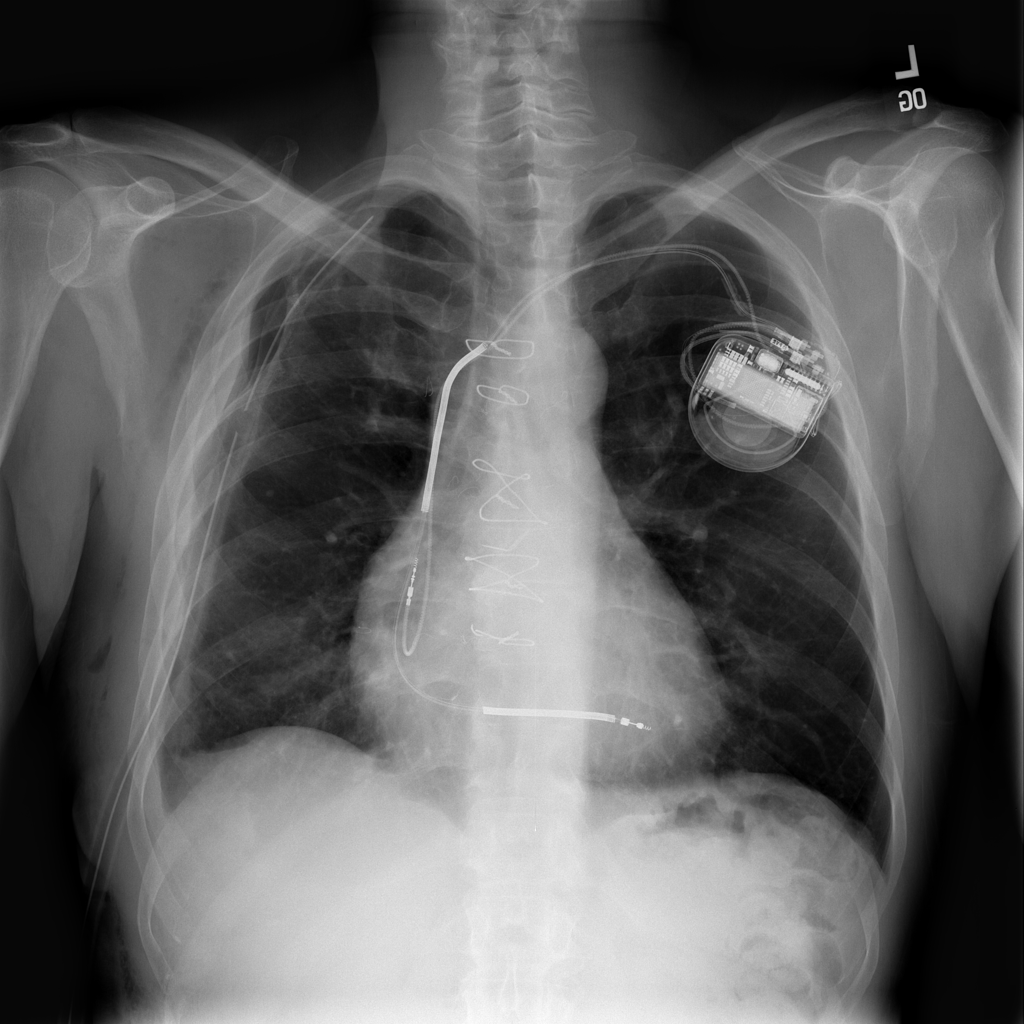

Showing up to 90 reference images for Pneumothorax.

PAT-4639 · IMG-012Pneumothorax

PAT-4639 · IMG-012

AP